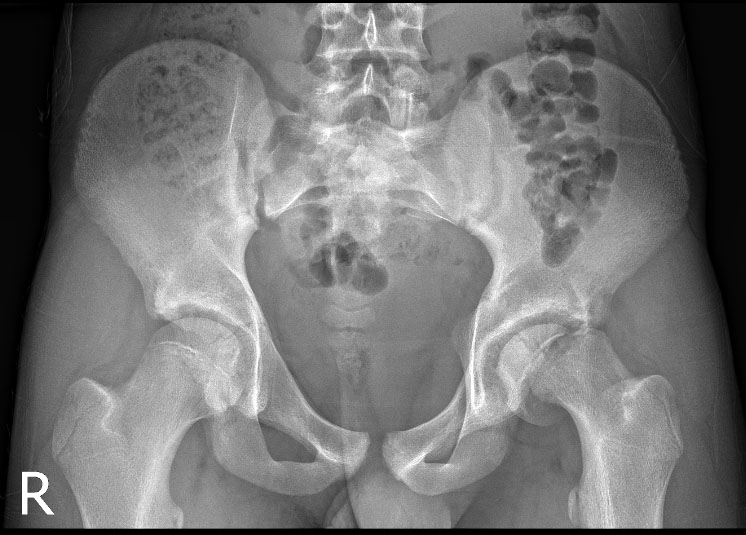

Nakon razgovora u ambulanti i na osnovu kliničkog pregleda djeteta može se posumnjati na poskliz glave bedrene kosti. Djeca opisuju intenzivne bolove u kuku, natkoljenici ili koljenu koji su se javili naglo, obično nakon neke aktivnosti. Bolovi mogu biti toliko jaki da dijete šepa ili čak ne može hodati. U kroničnom obliku poskliza bolovi nisu nagli i pretjerano izraženi već se djeca žale na manje bolnosti i nelagodu u kuku ili natkoljenici do koljena. Kod poskliza djeca nemaju povišenu tjelesnu temperaturu i dobrog su općeg stanja. Za vrijeme kliničkog pregleda dijete treba poleći na stol i provjeriti opseg pokreta u kuku. Fleksija kuka je promijenjena – koljeno „bježi vani“ dok je unutarnja rotacija kuka izuzetno bolna. Staro je pravilo dječje ortopedije da se kod svih bolova u koljenu treba pregledati i kukove. Osnovna dijagnostička obrada je RTG kukova u dva smjera, gdje se na RTG snimkama traži pomak glave bedrene kosti u odnosu na vrat, slika 1. Ponekad kod manjih i kroničnih poskliza RTG snimka nije dovoljna pa je potrebno napraviti MR. Druge bolesti koje u svom početku mogu uzrokovati slične tegobe na kuku su tranzitorni sinovitis kuka, septički artritis kuka, stres prijelom vrata bedrene kosti ili juvenilni idiopatski artritis kuka.

Slika 1.